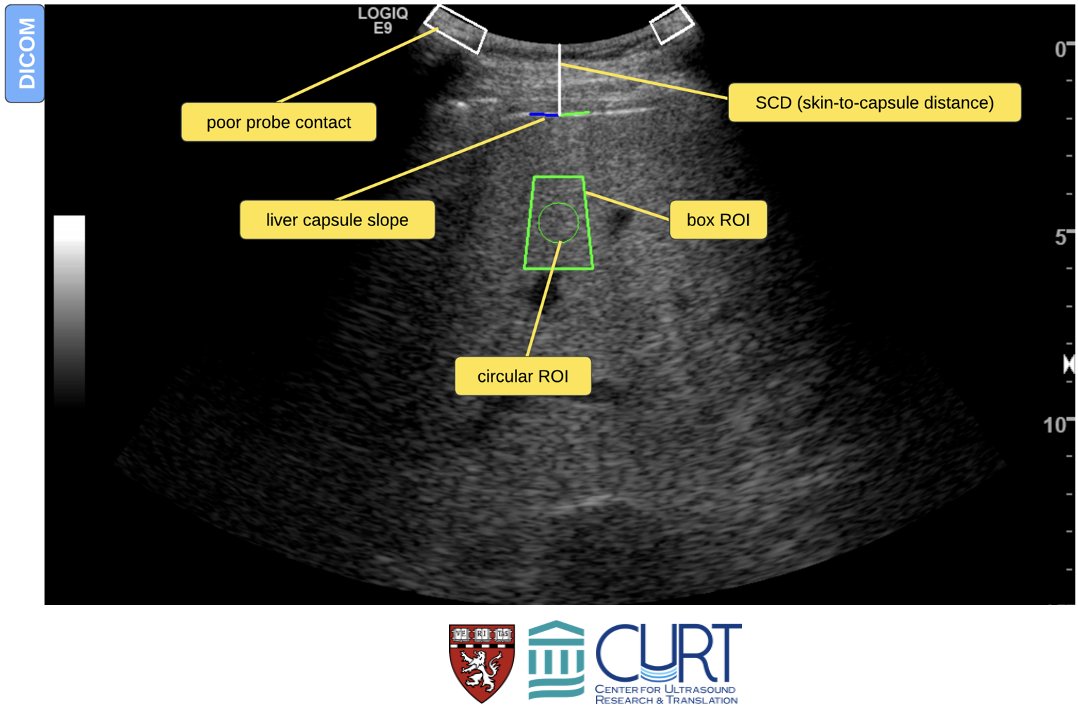

Our paper is now online in Radiology. It’s an honor to share the first authorship with my friend and mentor Dr.Pierce, under guidance of kathrynfowler and (((Anthony Samir))). Thank you Foundation for the National Institutes of Health NIMBLE consortium members for this opportunity! Radiology pubs.rsna.org/doi/10.1148/ra…

Thrilled to be speaking at the "AI in Tele-echography" workshop IEEE BHI 2025!, where I will be sharing some insights on "AI meets liver ultrasound imaging" and how AI is transforming liver diagnostics. IEEE Engineering Medicine and Biology Society